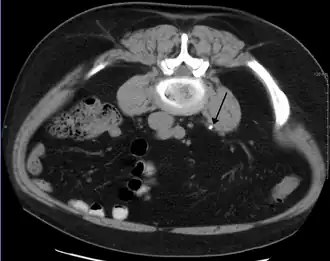

CT-scan van de buik met een steen van 3 mm in de linker ureter (pijl)